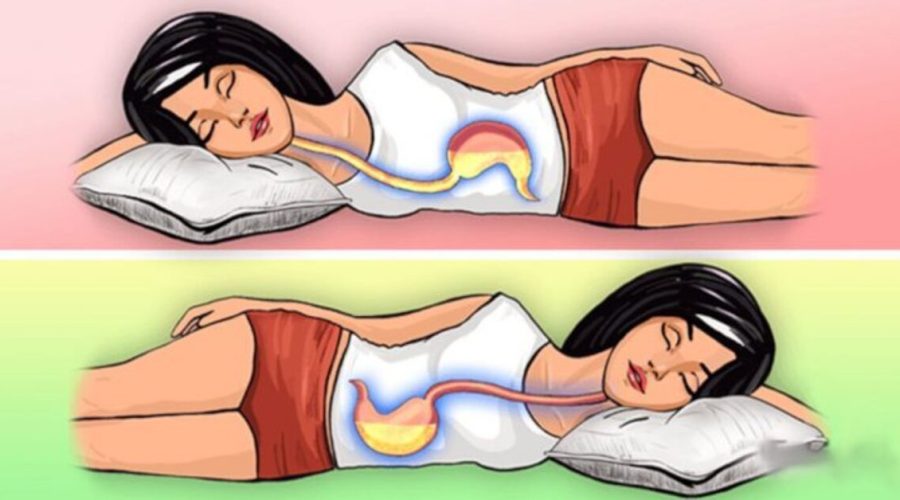

Continue lendoDescubra o por que devemos evitar dormir apoiados pelo lado direito do corpo

O sono é uma parte essencial de nossa rotina diária, e a forma como dormimos pode ter um impacto significativo em nossa saúde. Embora a […]